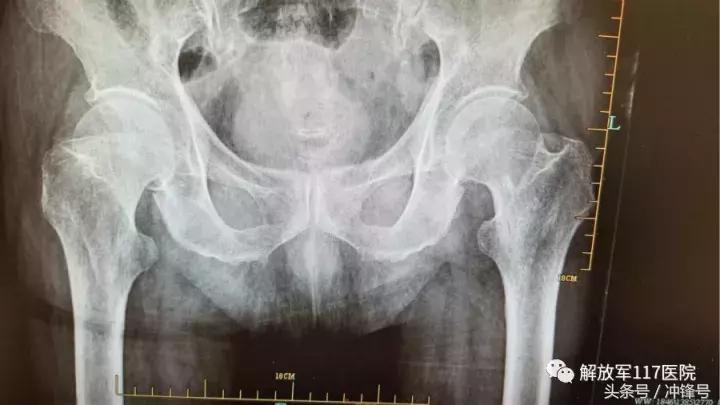

股骨颈骨折X光片

患者李承恩家住杭州市三里亭,虽然已是99岁高龄,但平常身体健硕,可自行起居。入院4天前,老人在走路时不慎摔倒,当时即感觉右髋部剧烈疼痛,无法活动,更不能起身。在家休养2天后,不仅疼痛没有明显好转,而且老人精神状态也每况愈下,还出现少量咳嗽。为避免病情恶化,家人随即将其送往解放军第117医院机场路院区急诊。急查胸部CT,骨盆平片,腰椎正侧位片等相关检查,提示两肺多发纤维条索灶,两侧胸膜增厚,右股骨颈骨折,腰椎平片显示L3/L4椎体压缩性骨折,随即以“右股骨颈骨折”转入骨三科作进一步诊治。